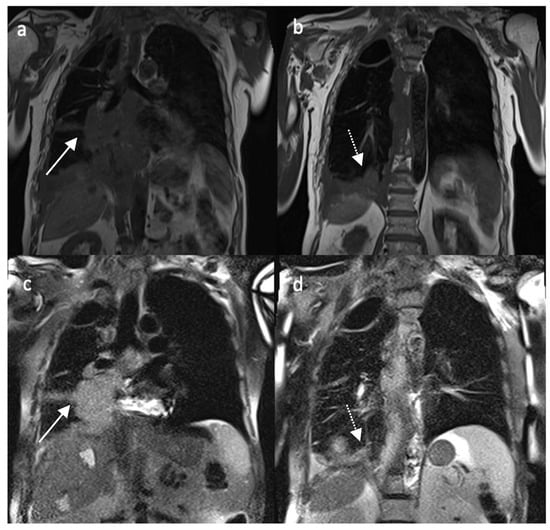

4.1. Morphological Evaluation

4.2.2. Contrast Enhancement-MRI